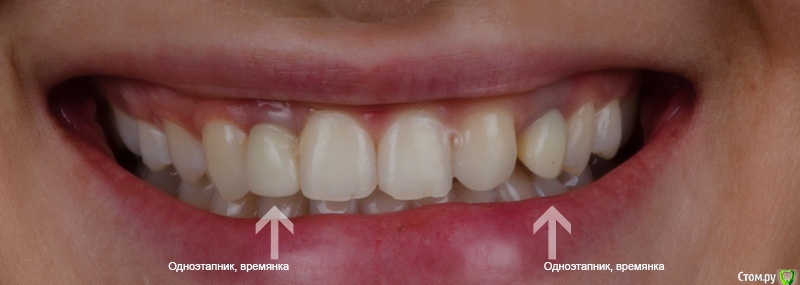

Паращук Роман Опубликовано 14 ноября, 2018 Поделиться Опубликовано 14 ноября, 2018 Работать от 13 по 23. Поднять зинит у 12. Увеличив дистальный валик 11 21,визуально уменьшить зубы в позициях 12,22. 13-винир,23 коронка,дистально возможно трема. Нужен воск от выше предложенного и смотреть. 2 Ссылка на комментарий

Romanson Опубликовано 14 ноября, 2018 Автор Поделиться Опубликовано 14 ноября, 2018 2.2 (на месте которого клык) превращать в двойку?Работать от 13 по 23. Поднять зинит у 12. Увеличив дистальный валик 11 21,визуально уменьшить зубы в позициях 12,22. 13-винир,23 коронка,дистально возможно трема. Нужен воск от выше предложенного и смотреть. Ссылка на комментарий

Борис80 Опубликовано 13 ноября, 2018 Поделиться Опубликовано 13 ноября, 2018 12 нессиметричен будет. идеального решения в такой ситуации нет, Буквально сегодня консультировал пациентку с практически такой же ситуацией... договорились что выберем вариант по ваксапу( 2 варианта, в первом случае клык "перетачиваем" в резец и в области 23 делаем клык, второй вариант 12 и клык слева не трогаем в области отсутствующего 23 моделируем премоляр с не выраженным небным бугром), но склоняемся к тому, что 12 и 23(который на месте 22) под виниры и в области 23 коронка в виде клыка Ссылка на комментарий